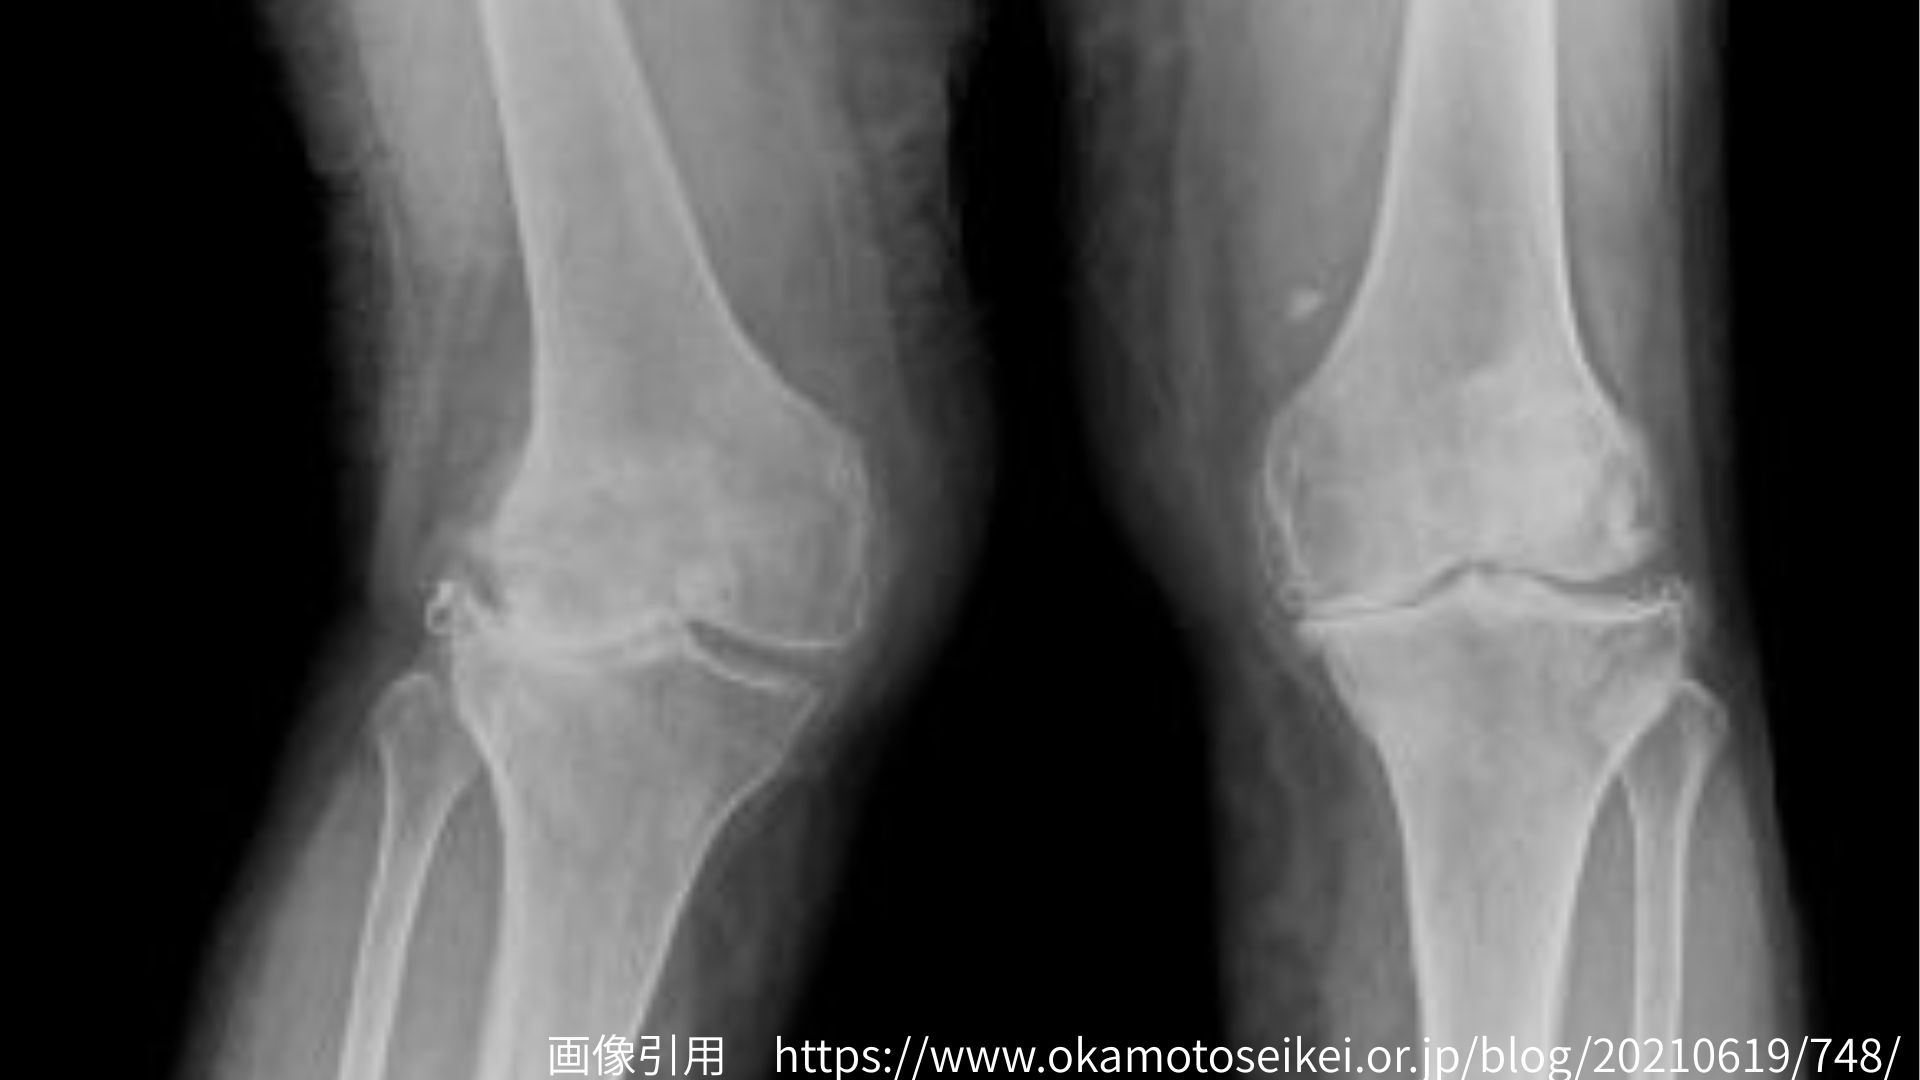

1.X脚が整体で変わらないケース ― 骨実質の変形 ―

成長期や外傷後などで、大腿骨や脛骨そのものの形に変形がある場合、骨格自体のアライメントが変わってしまっているため、整体だけでの矯正は難しくなります。

このようなケースでは、骨の構造に合わせて筋や関節の動きを整えるサポートを行うことで、痛みや歩行動作の安定を目指します。変形そのものを戻すのではなく、「機能的に動ける身体」に導くことが重要です。また、後述する軟部組織の問題が重複している場合(骨の変形+軟部組織の問題)が多いので、これらの問題を取り除くことでX脚は部分的な改善が期待できます。